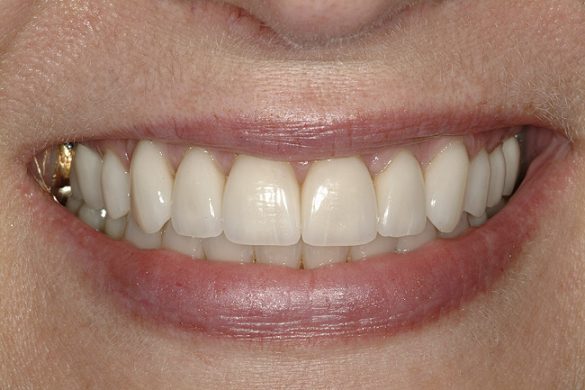

Deprogramatorul Kois a servit ca un instrument convenabil pentru diagnosticul şi managementul predictibil al cererilor funcţionale prezente. A trecut peste 1 an de când s-a finalizat tratamentul pacientei. Durerile de cap nu i-au revenit şi ea raportează că încleştarea şi scrâşnitul s-au abolit. Este foarte mulţumită de estetica finală (fig. 14-17) şi de rezultatul de succes al cazului (fig. 9). Prognosticul global este îmbunătăţit datorită reducerii riscurilor funcţionale şi biomecanice.